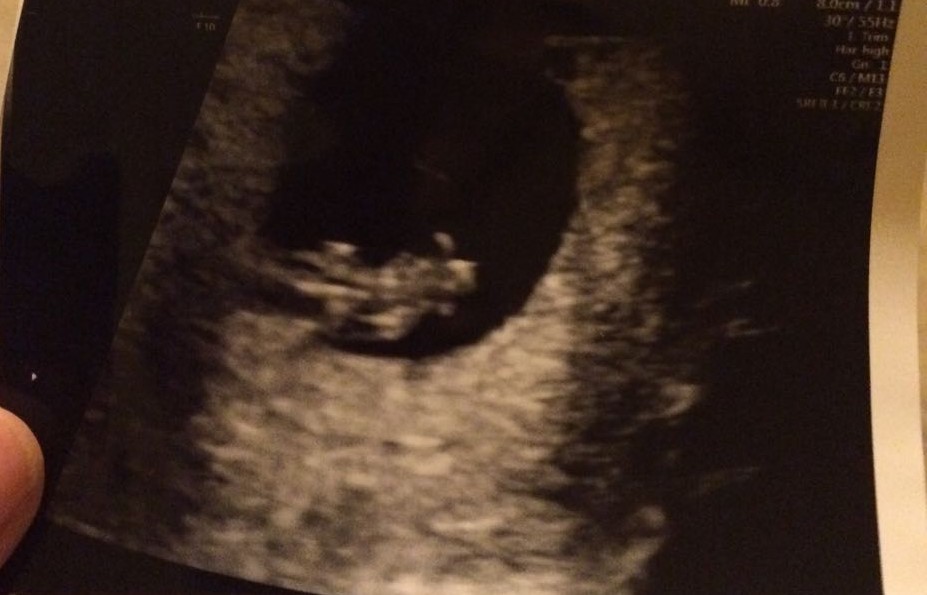

8+5 weeks

Attachment 28531